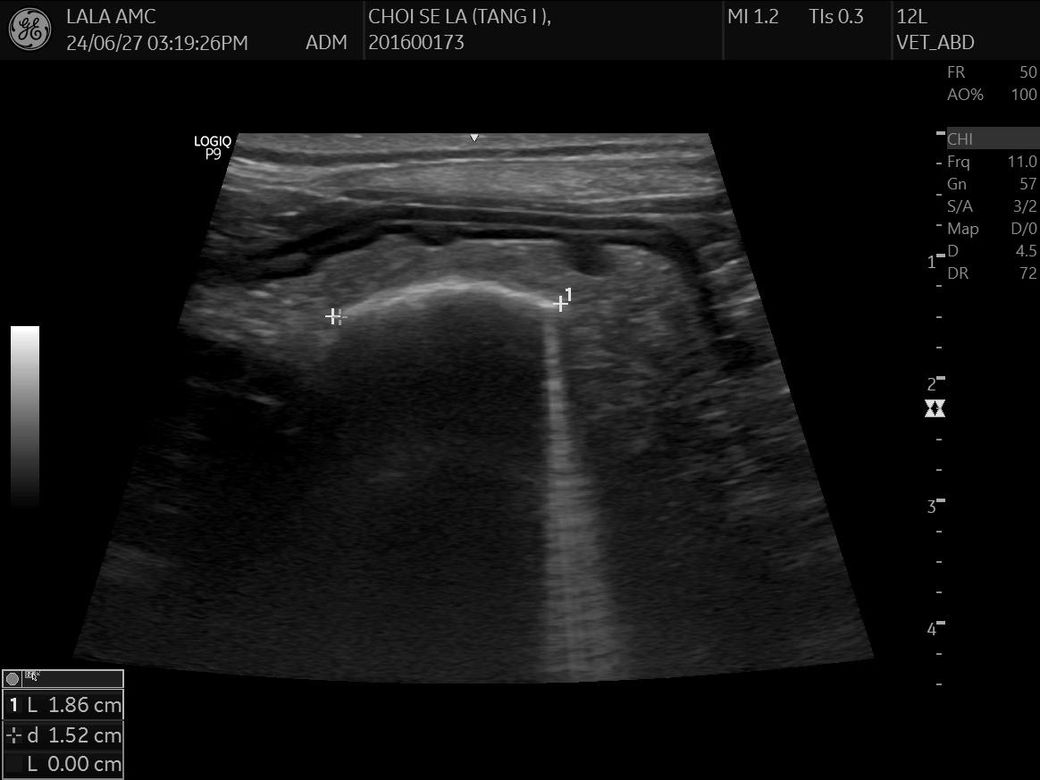

건강검진 하면서 초음파를 찍었는데

강아지 몸속에 1.8cm 물체인지 뭔가가 보인다고 합니다 건강검진은 아무이상 없었구요

저것만봐서는 물체가 있는것같나요?

크기와 반사 계면의 강도, 모양을 볼때 자두씨로 판단됩니다. 내시경을 통해 십이지장으로 넘어가기 전에 꺼내주는걸 추천합니다.